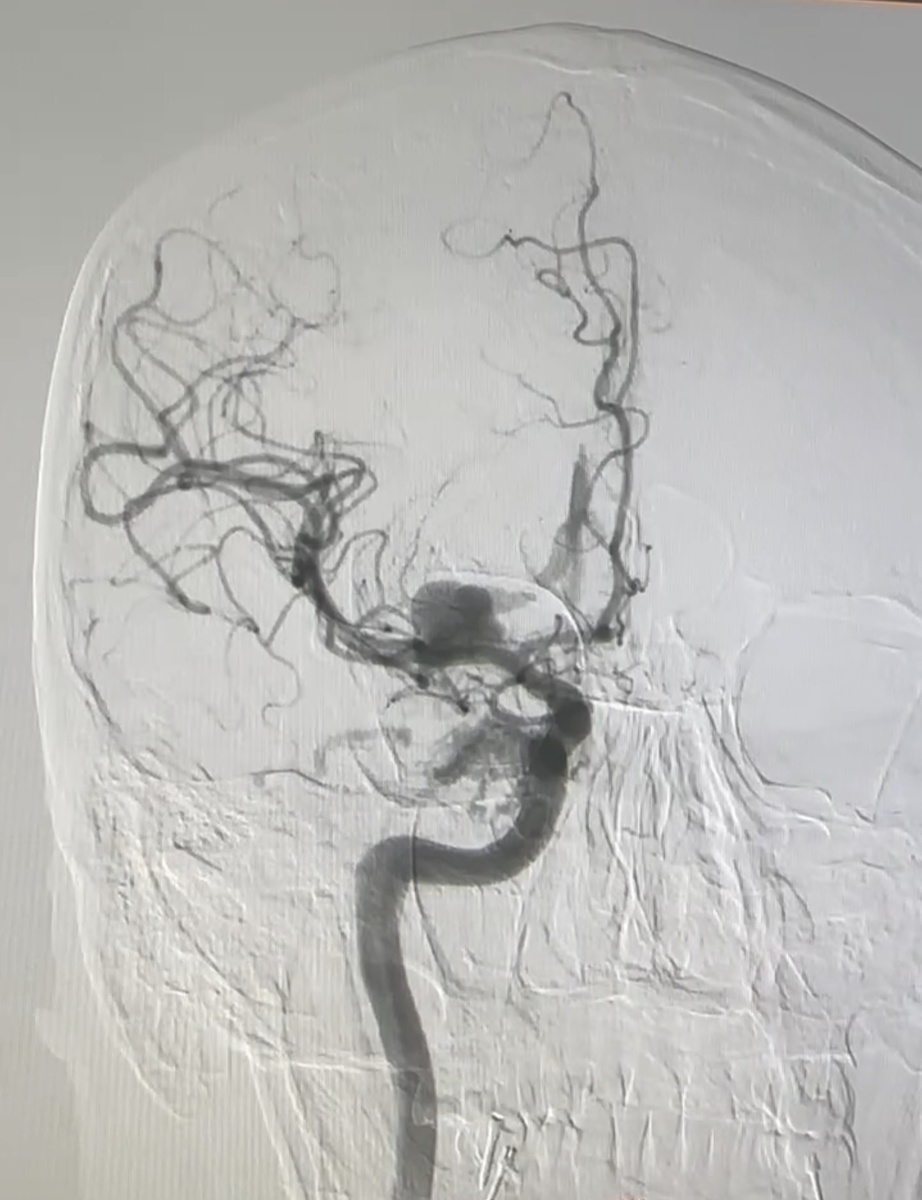

5. Селективная церебральная ангиография. Считается мини-операцией, инвазивная процедура. Чаще используется именно в нейрохирургии, только по строгим показаниям и с краткосрочной госпитализацией в стационар. Через бедренную артерию (пациент под масочно-пропофольным наркозом) пациенту вводится длинный тонкий проводок по сосудам, а также контраст. И, ползя по сосудам изнутри и подсвечивая контрастом, врач идеально видит до мельчайших деталий всю ситуацию с сосудистой системой. Используется при аневризмах сосудов головного мозга, инфарктах, расслоении аорты и проч. После процедуры пациент лежит 12 часов с грузом на бедре фактически неподвижно, чтобы избежать накопления гематомы в месте, куда вводили катетер.

P.S. фото из личного архива. На прикреплённой фотографии - прямая селективная церебральная ангиография сосудов головного мозга пациента с крупной аневризмой.